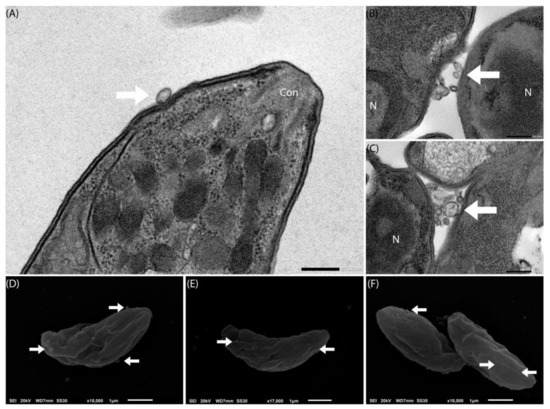

4.9. Assessment of T. gondii by Electron Microscopy